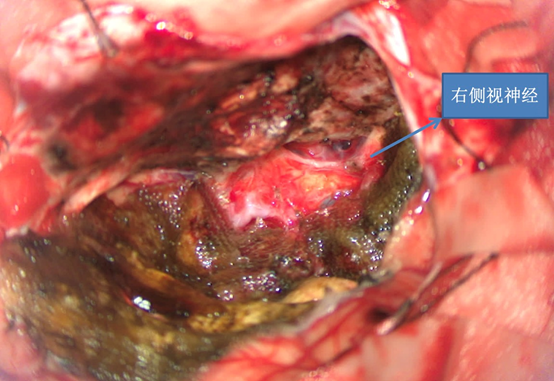

前颅窝底脑膜瘤常起源于前颅底筛骨筛板处的硬膜,瘤体多为双侧生长,少数为偏侧生长,女性稍多于男性。肿瘤可累及鸡冠和蝶骨平台的任何区域,是前颅窝肿瘤中最多见的一种。因为肿瘤位于前颅窝底,额叶在功能上属于“哑区”,患者就诊发现肿瘤时瘤体多已巨大。主要症状可有颅内压增高症状、视力减退、癫痫以及精神症状等。该患者主因“左眼失明10个月,头痛3个月”就诊。术中采用双额冠状开颅,左侧为主,由于肿瘤体积巨大,术中切除少许薄层额叶脑组织,边离断基底、边瘤内减压,分块切除肿瘤,最终探查肿瘤基底主要位于鸡冠、筛板、蝶骨平台、鞍结节、前床突处硬膜,术中见肿瘤供血主要来源于前颅窝底硬膜及大脑前动脉分支,术中仔细辨认供血动脉、过路血管,大脑前动脉及其分支保护完好,术中见视神经、视交叉受压明显,尤其是左侧视神经已缺血苍白,最终达Simpson II级切除。术者体会,该患者术前行多模态重建,可见瘤表数条粗大的静脉,术中切莫过早离断肿瘤的引流静脉,以防因引流不畅致瘤体肿胀出血;术前行多模态重建,利于鉴别供血动脉、过路血管,早期离断供血动脉更利于肿瘤切除;该类肿瘤基底一般较为广泛,不能盲目离断基底,尤其是近鞍结节处,可以于中线处离断基底,进入第一间隙后向两侧探查并保护视神经,待充分缩小瘤体看清楚毗邻的血管神经后再将其完全切除;术毕做好多层颅底重建以防脑脊液漏。另外,该患者术前左眼失明已达10个月,术后第1天即有光感,术后1月复查左眼视力可达50cm内数指,这在临床中非常少见,对于此类病人,不要轻易放弃挽救视力的任何机会。